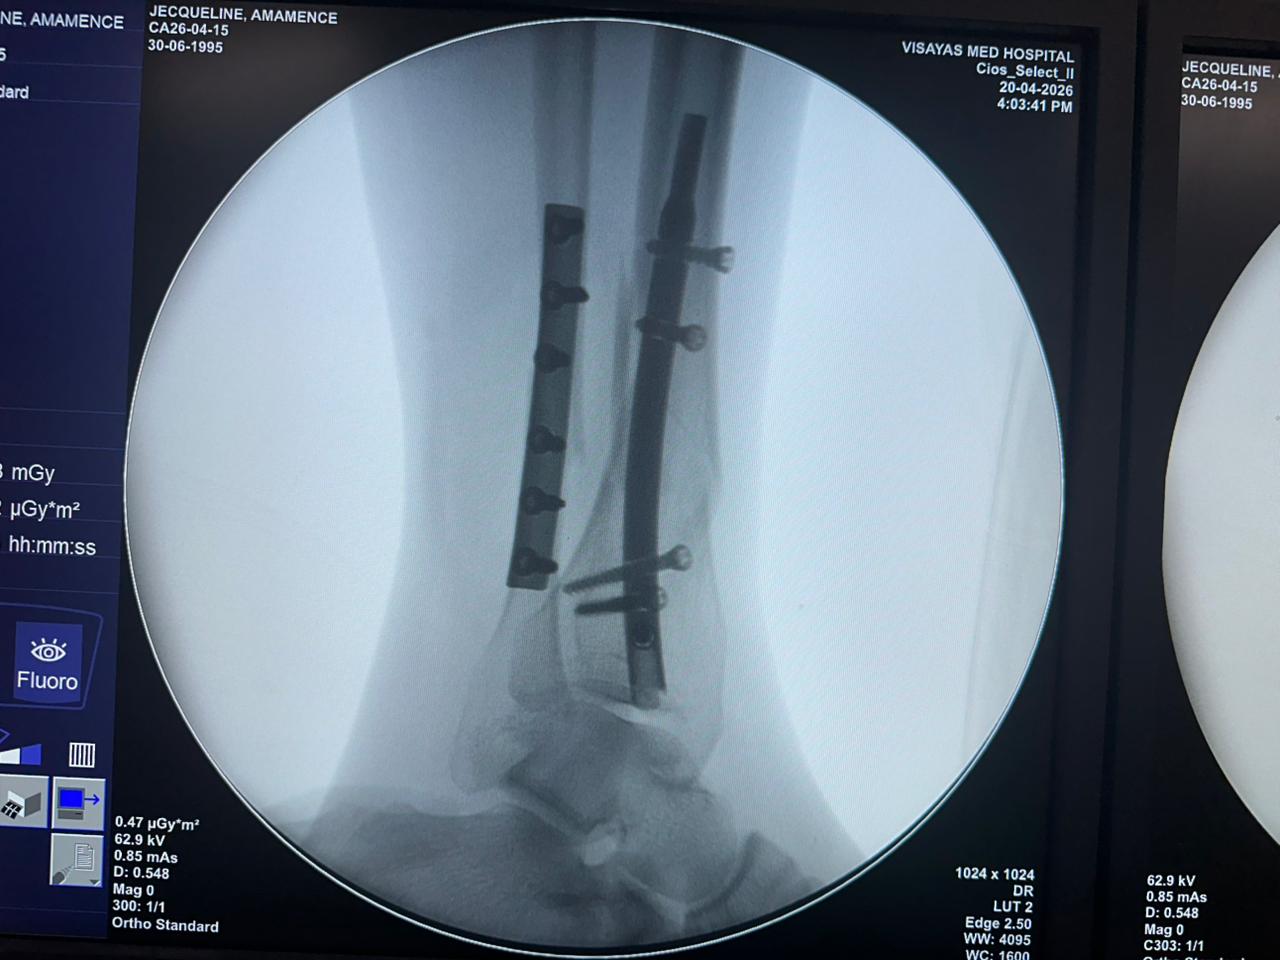

Distal Tibial Nail Fixation Case Study with Fibular Plate Support

Patient:

31-year-old patient

Surgical Area:

Distal tibia and fibula

Product Used:

Distal Tibial Nail

Fibular Locking Plate

Imaging:

Intraoperative C-arm fluoroscopy, AP and lateral views

Case Summary:

This case involved distal tibial fixation using an intramedullary distal tibial nail. Intraoperative fluoroscopy confirmed the position of the nail, distal locking screws, and fibular plate fixatio